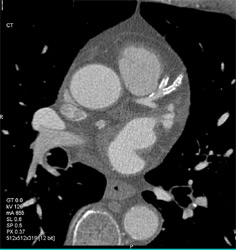

Diagnosis

Diseased LAD